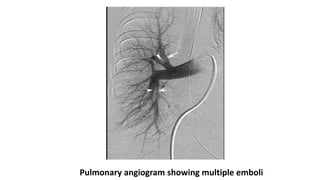

Pulmonary Angiogram- Gold Standard

• Pulmonary angiography remains the accepted “gold standard” for PE

diagnosis.

• Only two angiographic findings are diagnostic of acute embolism: the

filling defect and abrupt cutoff of a vessel.

• Catheter is inserted in the right heart and dye is injected into

pulmonary trunk. Filling is observed under fluoroscopy.

• Limitations of Pulmonary Angiogram

• It requires expertise in study performance and interpretation;

• it is invasive.

• High mortality due to procedure itself.

Pulmonary angiogram showing multiple emboli

Pulmonary Angiogram- GoldStandard • Pulmonary angiography remains the accepted “gold standard” for PE diagnosis. • Only two angiographic findings are diagnostic of acute embolism: the filling defect and abrupt cutoff of a vessel. • Catheter is inserted in the right heart and dye is injected into pulmonary trunk. Filling is observed under fluoroscopy. • Limitations of Pulmonary Angiogram • It requires expertise in study performance and interpretation; • it is invasive. • High mortality due to procedure itself.